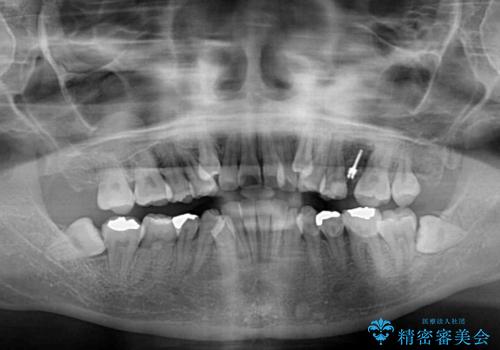

デコボコが強いため、非抜歯で矯正をすると出っ歯仕上がりとなるため、上下左右の第一小臼歯4本を抜歯することとしました。